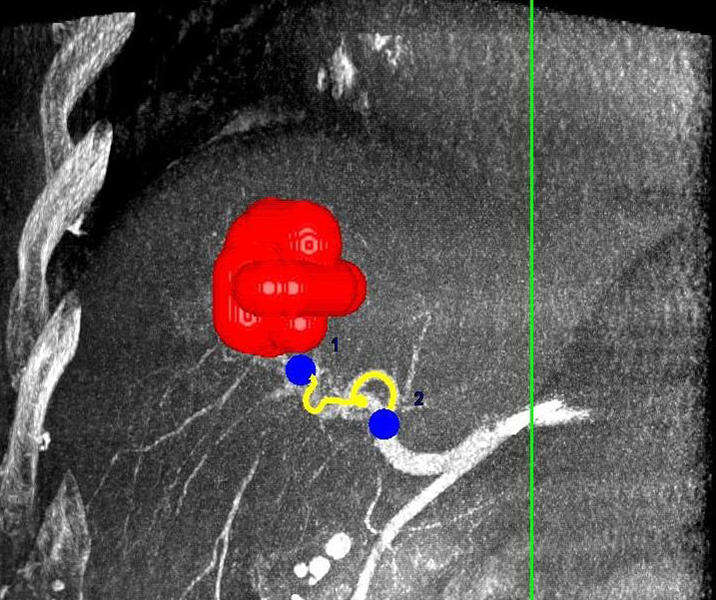

Präoperative Tumormarkierung

Eine Voraussetzung für die vollständige chirurgische Entfernung von Knochen- und Weichteiltumoren ist die präzise Erkennung der Tumorausdehnung und der Tumorgrenzen. Mit der Kernspintomographie (MRT) kann das Tumorgewebe exzellent von gesundem Gewebe abgegrenzt werden und somit die Ausdehnung vor der Operation bestimmt werden. Nach der kernspintomographischen Bestimmung der Tumorausdehnung werden unter kontinuierlicher MRT-Bildgebung die Grenzen des Tumors markiert. Die Marker werden mit einer Nadel ins angrenzende gesunde Gewebe eingebracht. Die Markierung kann am Tage vor der Operation durchgeführt werden. Alternativ ist die Tumormarkierung auch mit anderen bildgebenden Verfahren möglich, z.B. mit der Computertomographie oder dem Ultraschall.

Abbildung: Bei diesem Patienten wurde ein im Röntgen nur schlecht sichtbarer Knochentumor vor der Operation unter MRT-Kontrolle mit kleinen röntgendichten Spiralen („Coils“) markiert. Damit hat der Operateur eine optimale Darstellung des Tumorbereichs bzw. der Tumorgrenzen und kann gezielter, schonender und effektiver operieren.